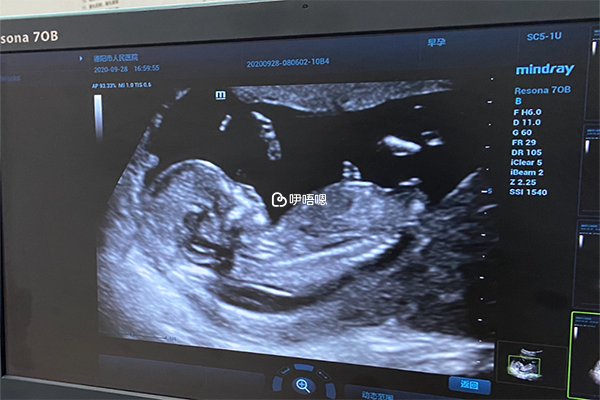

凍胚移植第38天孕囊的大小在3cm左右,此時B超下觀察胎芽在1.5cm左右,因為移植38天相當於已經正常懷孕8周了,所以這個時期就不能按照孕囊大小計算了,需要按照胎芽或者頭臀徑計算。

孕8周時胎兒長到1.66釐米,胎形已定,可分出胎頭、體及四肢,胎頭大於軀幹。B超可見胎囊約佔官腔1/2,胎兒形態及胎動清楚可見,並可看見卵黃囊。